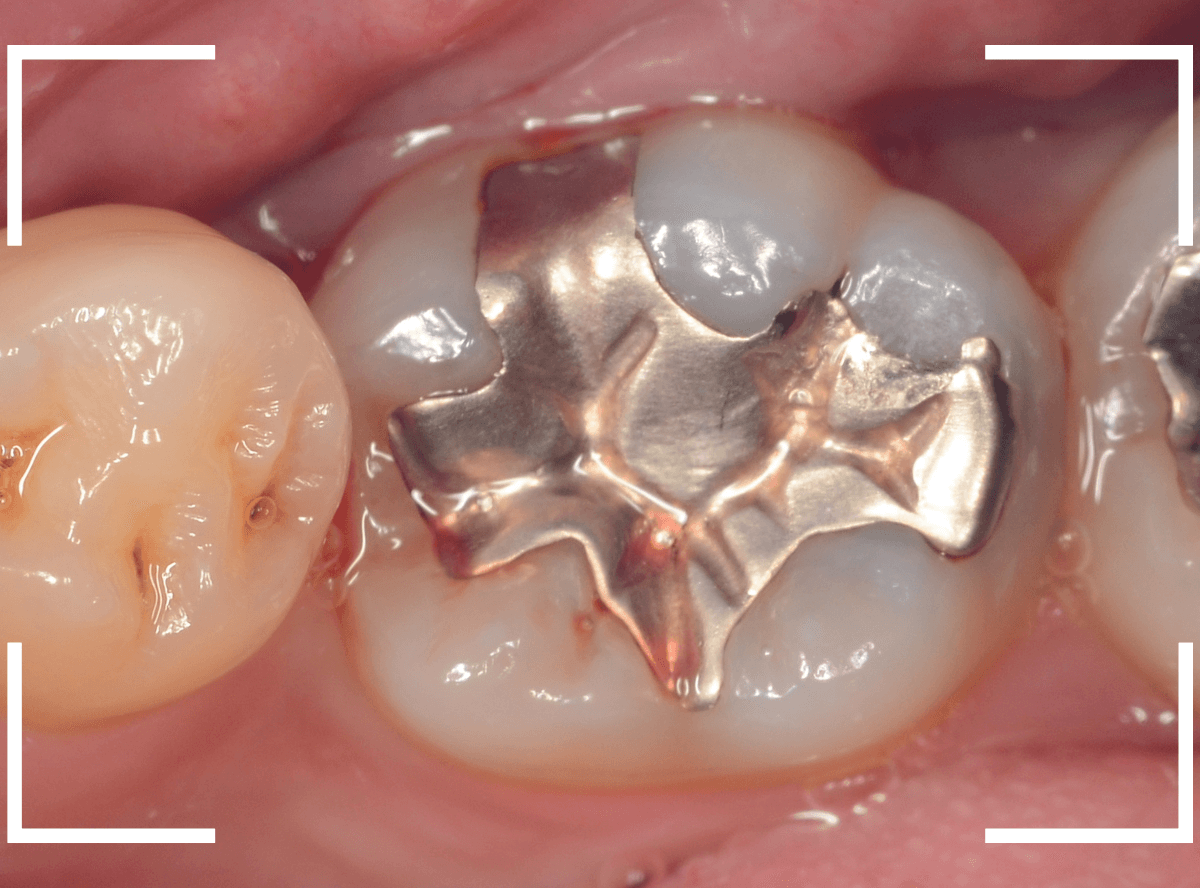

Case.12 金属のつめものの下の状況がわからない

定期メンテナンスに通っていらっしゃっている患者さんです。

金属のつめものが若干不適合気味になっているのと、その周りが黒くぼやっとなっていて怪しいですが、金属色が透けているのか虫歯になり始めてるのか、よくわかりません。

レントゲン写真で確認します。

虫歯があるのかはっきりしない写り方です。

患者さんに状況を説明の上、つめものを外して調べてみる事にしました。

つめものを外すと、虫歯が出てきました。

金属のつめものの下に、アマルガムという金属がつめてあるのも見られます。

あとは、少しずつ削りながら、虫歯を調べます。

全ての虫歯を除去しました。

幸い、あまり大きく歯を削らずに済みました。

早いうちに治療が出来てよかったかと思います。